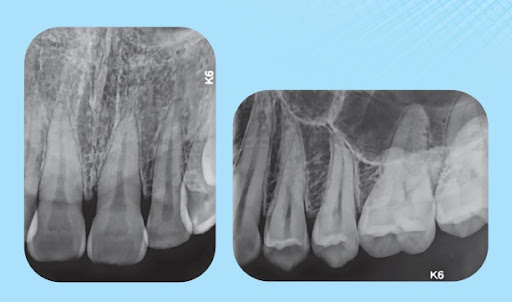

Các dòng máy X-quang cầm tay hiện nay, như ProX hay Handy HDS-500, đều được trang bị công nghệ tiên tiến cho ra hình ảnh sắc nét, độ phân giải cao. Nhờ vậy, bác sĩ dễ dàng phát hiện sâu răng, bệnh nha chu, hay vị trí chân răng khi cắm implant.